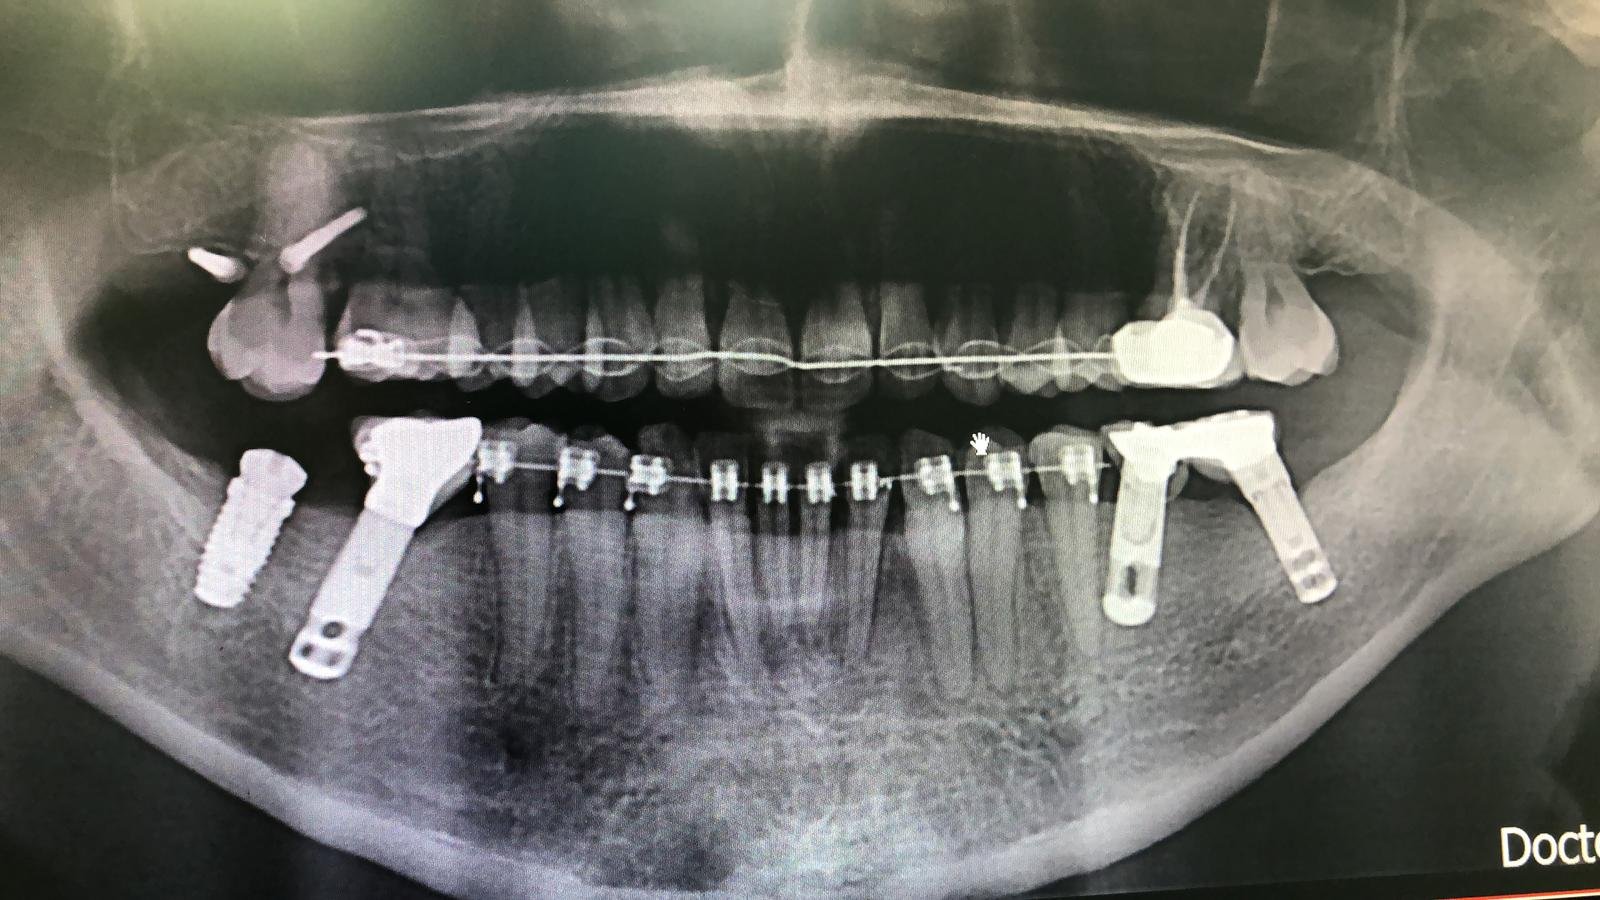

Duda marca y diámetro de implantes en sector anterior.

Paciente de origen colombiano que acude a consulta con 4 implantes colocados en sector anterosuperior en posiciones #12, #11,#21 y #22. Necesitamos conocer la marca y diámetro de los implantes [...]